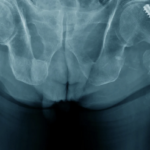

Does maximizing bearing diameter markedly lower dislocations among primary total hip arthroplasty (THA) patients?

The researchers reviewed data on all patients who underwent fixed-bearing THA at NYU Langone Health between 2016-2022. They noted which patients received the largest bearing available from any manufacturer for the acetabular diameter. Larger cups were excluded.

Bearing diameter was maximized in 835 of 8607 patients, whereas 7309 patients received the second-largest bearing available. There were 79 dislocations; however, none occurred with maximized bearing diameters. Dislocation risk also varied with intraoperative technology use, surgical approach, and liner geometry.

In a sub-analysis of 4185 patients with smaller bearings who underwent THA by the posterior approach, liner geometry did not impact dislocation odds. Receiving the second-largest available bearing also did not demonstrably reduce dislocation odds compared with smaller bearings.

“Utilizing the largest available bearing, within 14 millimeters of the cup diameter, is associated with markedly reduced odds of dislocation. Advanced technology and stable surgical approaches mattered also, but bearing diameter had the largest effect size.”